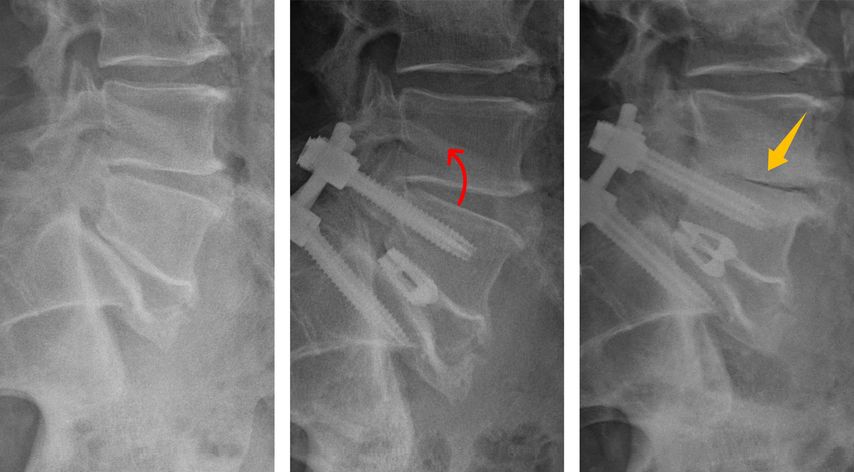

In den vergangenen Jahren hat sich das Verständnis der sagittalen Wirbelsäulenparameter deutlich erweitert und dieses Wissen findet zunehmend Anwendung im klinischen Alltag. Neben klassischen Messgrößen wie der Lendenlordose oder der Beckenneigung werden zunehmend auch individuelle patientenspezifische Zielwerte herangezogen. Aber nicht nur die globale Balance der Wirbelsäule ist hier von großer Bedeutung. Auch bereits eine Deformität eines einzelnen Segmentes kann maßgeblich sein. Eine fehlende oder unzureichende Lordose im operierten Indexsegment zwingt angrenzende Segmente in pathologische Kompensationsmechanismen, um das sagittale Gleichgewicht zu erhalten. Die hierbei auftretende Hyperlordose und Retrolisthese im Nachbarsegment führt zu unphysiologischen biomechanischen Belastungen der Bandscheibe und Facettengelenke (Abb. 1). Dies kann ein Mechanismus und Treiber der „Anschlussdegeneration“ sein. Eigene Untersuchungen zeigten, dass eine konsequente Wiederherstellung der Lordose nach einer monosegmentalen Fusionsoperation das Potenzial hat, die Kompensationsmechanismen im direkt angrenzenden Segment deutlich zu reduzieren (Abb.2 ). Auf solche Erkenntnisse sind zunehmend auch Implantathersteller eingegangen und bieten neue Implantate an, die helfen sollen, die Lordose wiederherzustellen. So finden sich etwa zunehmend hyperlordotische Cages für ventrale wie auch dorsale interkorporelle Verfahren am Markt und eröffnen zusätzliche Möglichkeiten, die sagittale Balance individuell anzupassen.

Abb. 1: Schematische Darstellung von Kompensationsmechanismen (a) mit unphysiologischen Belastungen (b) im kranialen Nachbarsegment bei segmentaler hypolordotischer Deformität L5/S1 sowie Reduktion derselben bei Wiederherstellung der Lordose durch interkorporelle Fusion (c)

Abb. 3: Beispiel einer zunehmenden Degeneration im Segment L4/5 nach Spondylodese im Segment L5/S1: Eine multifaktorielle Ursache bei segmentaler Hypolordose im Indexsegment mit kompensatorischer Hyperlordose und Retrolisthese im kranialen Nachbarsegment, Adipositas und Nikotinabusus kann postuliert werden